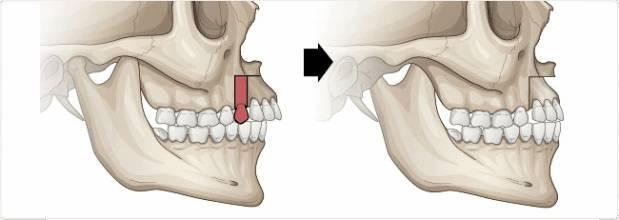

经过矫正以后,凸出的牙齿回缩到正确的位置,龅牙问题就可以解决了

包括一些牙齿排列不齐的问题,只要通过矫正就可以解决了

所长动手把骨性问题的牙齿往回收了收,但是效果也仅限于此

牙性的可以做正畸就不具体说了,可以选择的矫正器有很多种,金属的、陶瓷的、隐形的都有(具体了解如何选择牙套戳这里)

根据不同程度的问题,矫正时间几个月到几年的都有,并且校正后需要佩戴保持器,保持新的牙齿位置,等待牙槽骨改建,医生一般要求佩戴时间越长越好(成年矫正者需3-5年不等)

保持器佩戴时间:矫正后3-6个月内每天佩戴(20小时以上),3-6个月后每天晚上佩戴(10-12小时左右)